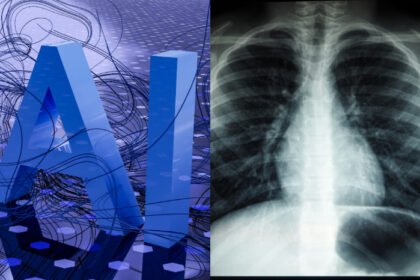

La detección oportuna con inteligencia artificial disminuye la mortalidad por cáncer de pulmón

Avances en la Detección del Cáncer de Pulmón en México La detección…